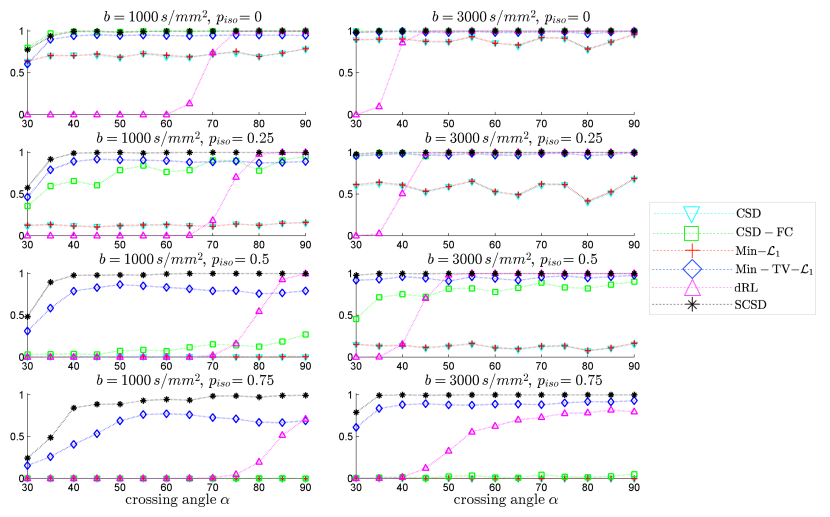

The left and right columns of subplots in Fig. 4 show the values of AAE as a function of crossing angle , which have been obtained with the proposed and reference methods for s/mm2 and s/mm2, respectively. The regularization parameters for Min-, CSD-FC, Min-TV-, and SCSD were set to optimize the overall performance of the algorithms, namely: 1) for Min-, 2) for CSD-FC, 3) , for Min-TV-, and 4) , , for SCSD. The dRL method has been reproduced following its description in [44]. One can see that all the error curves, with the exception of that of dRL, exhibit the expected behaviour where AAE decreases with an increase in . Moreover, despite the substantially worse noise conditions for s/mm2, all the tested methods (again, with the exception of dRL) demonstrate better performance for s/mm2, as compared to the case of s/mm2. In all the cases, however, the proposed SCSD method shows considerably better performance in comparison to the alternative solutions, with the “second best” results produced by CSD-FC for lower values of and by Min-TV- for higher values of .

Before proceeding any further, one additional comment is in order regarding the behaviour of the AAE curves obtained with dRL. Specifically, one can see that, for s/mm2, the AAE is minimized for smaller values of , which is rather a counter-intuitive result. To understand why this happens, it is instructive to examine the behaviour of the TP curves produced by dRL (see Fig. 5). Specifically, one can see that for s/mm2 and , dRL is incapable of resolving the crossing fibres of the numerical phantom for , with the resolvability problem becoming progressively worse with an increase in . In this case, the values of AAE effectively “mirror” those of up to the point when dRL starts detecting the correct number of fibres, after which AAE becomes a decreasing function of the fibre crossing angle. It also deserves noting that for s/mm2, dRL demonstrates considerably improved performance in terms of AAE, even surpassing CSD and Min- for and . However, in all the alternative scenarios, the performance of dRL remains inferior to that of other methods under comparison. A possible explanation to this fact could be that the Lucy-Richardson algorithm exploited by dRL aims at recovering a maximum likelihood estimate under the assumption on measurement noise to be Poissonian. However, such a noise model can hardly be a good approximation to Rician distribution, which is inherent in MRI.

Fig. 5 shows the values of TP which have been obtained using the proposed and reference methods for s/mm2 (left column of subplots) and s/mm2 (right column of subplots). One can see that, in the absence of isotropic diffusion (i.e., for , the proposed SCSD method performs comparably to CSD-FC for both values of (with Min-TV- being the next “best performer”). Yet, the moment starts growing above zero, not only CSD and Min-, but also CSD-FC start loosing their ability to accurately estimate the true number of simulated fibres. Note that this is an expected result, considering the fact that neither of the above methods is endowed with facilities to explicitly account for the presence of isotropic diffision, in which case over-estimation errors become inevitable (see below). At the same time, for s/mm2, the proposed SCSD algorithm provides an ideal detection rate of one for and , as well as for and . It deserves noting that, owing to its properly accounting for the effect of isotropic diffusion, the performance of Min-TV- is only marginally inferior to that of SCSD for s/mm2 and . One can also see that a nearly ideal TP rate is reached by the dRL algorithm as well. However, it does not happen until after reaches relatively large values (e.g., for with and s/mm2).

One of the principle applications of HARDI is in multi-fibre tractography, in which case SD can be used to improve the resolvability of multiple fibre tracts within each given voxel in a region of interest (ROI). In this situation, overestimating the number of fibres is likely to produce spurious fibre tracts, thereby rendering the resulting reconstructions unreliable. Unfortunately, unless properly regularized, some SD routines tend to amplify the effect of noise, which in turn results in numerous false (local) maxima in reconstructed fODFs – the maxima that can be easily confused with the true modes of the latter. For this reason, it is important to compare the performance of SD routines in terms of the FP metric. Such comparative results are summarized in Fig. 6, the left and right columns of which correspond to the cases of s/mm2 and s/mm2, respectively. One can see that, in this case, the worst results are produced by CSD and Min- for all values of and . The CSD-FC algorithm, on the other hand, provides a close to zero FP rate for s/mm2 and . Unfortunately, its performance deteriorates for higher values of (which is particularly noticeable for s/mm2). Surprisingly, dRL seems to provide an ideal FP rate of zero for all values of and under consideration. However, from our analysis of Fig. 5 it is not hard to see that it happens only because this method tends to underestimate the true number of simulated fibres. Finally, one can also see that, for s/mm2, Min-TV- provides a fairly small FP rate, whereas the proposed SCSD algorithm succeeds to attain the ideal FP rate of zero for all values of and .